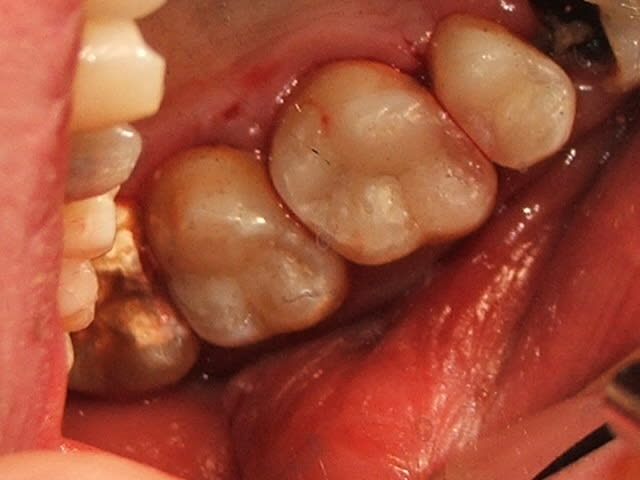

Voilà ce que je fais et les résultats.

C'est plus une surface de contact, et j'aurais dû utiliser un écarteur de Mc Kean sans doute.